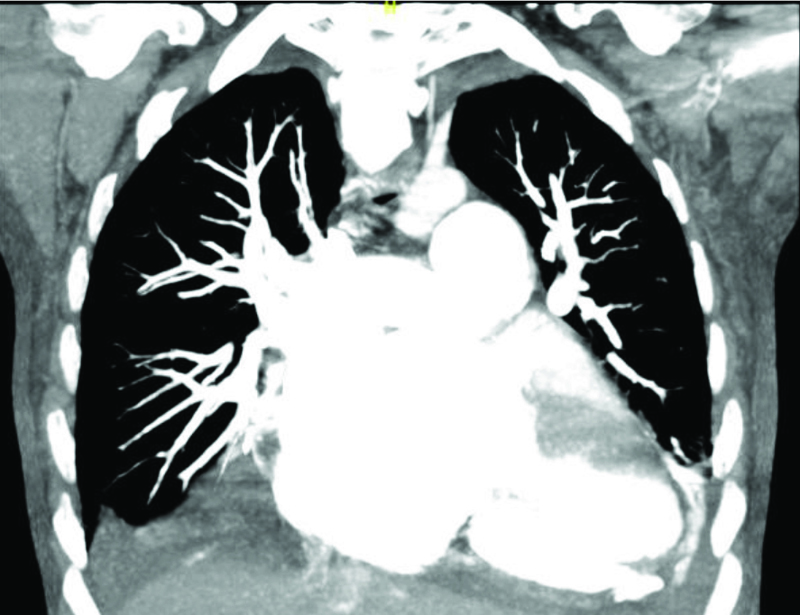

Laboratory results showed markedly elevated D-dimer levels at 10.5 mg/L (reference range: 0.19–0.50 mg/L). A chest x-ray indicated cardiomegaly with changes suggestive of pulmonary edema. Computed tomography with angiography revealed cardiomegaly with bilateral pleural effusions and diffuse dilatation of the pulmonary arteries, indicating significant pulmonary hypertension or overcirculation (Figure 1 and Figure 2). A transthoracic echocardiogram (TTE) identified a large secundum ASD with elevated right ventricular pressure measuring 70–74 mmHg. Flattening of the interventricular septum was also observed, further supporting the diagnosis of elevated right ventricular pressure. The TTE also revealed severe muscular and dynamic right ventricular outflow obstruction and pulmonary valvar stenosis. The patient was started on a diltiazem drip, and the cardiology service was consulted for transesophageal echocardiogram (TEE) guided cardioversion. The TEE confirmed the presence of a large ASD, and the bubble study indicated primarily left-to-right shunting, with a possible ventricular septal defect (VSD). Both atria appeared enlarged, but no intracardiac thrombus was detected. The patient underwent electrical cardioversion and successfully returned to sinus rhythm.

Figure 2

Figure 2. Coronal view of the thorax once again showing the diffuse enlargement of the pulmonary arteries.